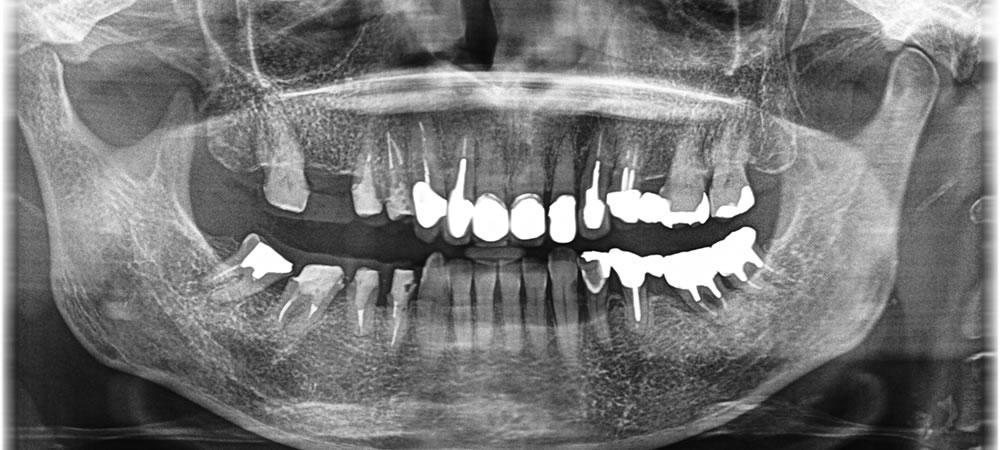

保存不可能な歯を抜歯して全顎的な咬み合わせを改善した症例

こちらの患者さまは、左下が噛めないとの主訴で来院されました。

診査・診断の結果、全体的に咬合状態が悪くなっていることが分かりました。患者さまと相談し、保存不可能な歯を抜歯後、インプラントなどによって上下の咬合状態を改善する計画を立てました。